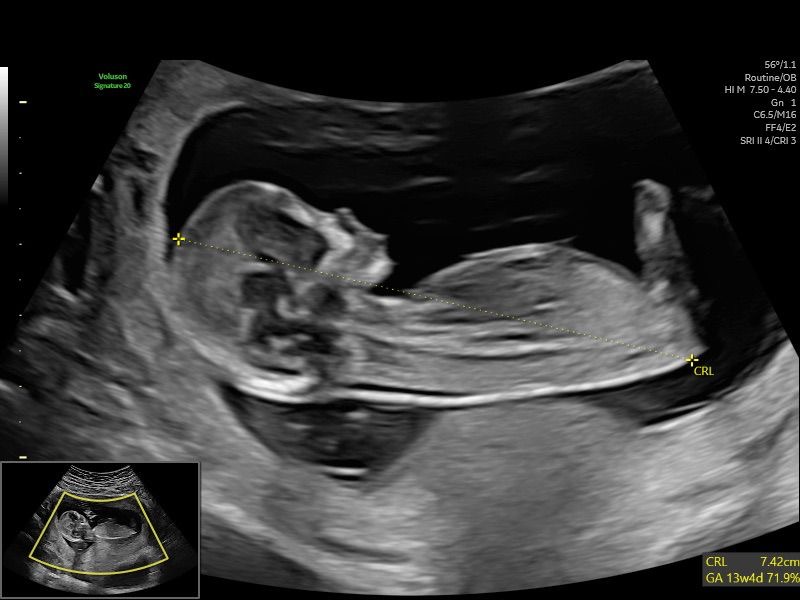

Early Pregnancy Scan (5-12 Weeks)

An early pregnancy scan is often one of the most reassuring steps in early pregnancy. At HerView, we understand that these first weeks can be both exciting and emotional, and many women simply want clarity, comfort, and a first connection with their growing baby. Our Early Pregnancy Scan, carried out…